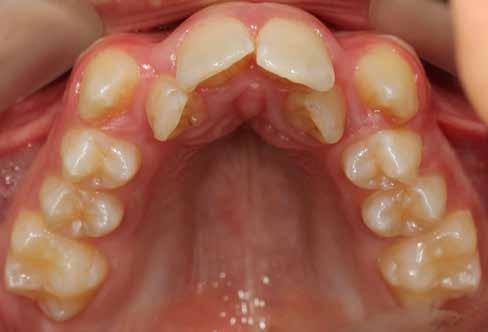

Ebben a cikkben egy 16 éves lánypáciens esetét szeretném bemutatni (1–7. képek)

A Pitts21-es fix készülékes kezelés során a harapásemelőket a felső nagyőrlő fogakra ragasztottuk, hogy a felső molárisok intrúziójával segítsék a harapás zárását (8. kép) Ún. keresztharapásos, majd később normál class 2-es gumihúzással (9–10. képek), továbbá az elülső fogakon alkalmazott ún. Rainbow harapás-záró gumihúzással (11. kép) korrigáltuk a jobb oldali teljes premolárisnyi distal-harapást, valamint az elülső nyitott harapást.

6 hónap után a nyitott harapás már nagyjából összezárásra került (12. kép)! A gumihordás a kezelés teljes hosszában folyamatos, éjjel-nappal, 22-24 órában az étkezések és az utánuk történő fogmosás kivételével.

A fix fogszabályozó készülék mindössze 16 hónapos kezelés után került eltávolításra! Páciensünk legnagyobb örömére állcsontműtét nélkül sikerült mind az arcesztétikai, mind a funkcionális rehabilitáció (13–18. képek)